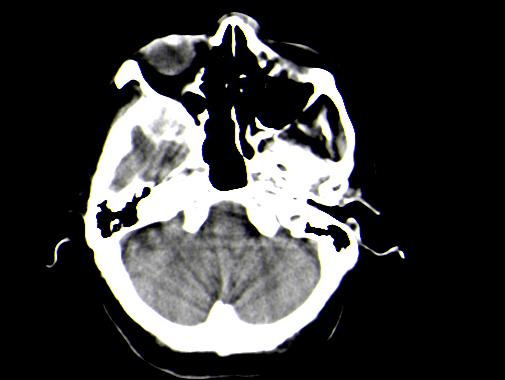

定位:右侧脑室三角区扩大,呈球形,侧脑室颞角扩大,右侧脑室内占位:

定位:右侧脑室三角区扩大,呈球形,侧脑室颞角扩大。

神经上皮囊肿为先天性疾病,可发生在脉络丛、脑室内、脉络膜裂,少数位于脑质内,侧脑室三角区最为常见。按发生部位和囊壁的细胞学类型可有不同的命名。位于脉络丛者为脉络丛囊肿,常两侧同时发生。脑室内者为室管膜囊肿,多位于侧脑室三角区。脉络膜裂囊肿可以是神经上皮囊肿,也可以是蛛网膜囊肿。 囊肿呈脑脊液样低密度,边界清楚整齐。患者多无症状,有症状者多为头痛、癫痫发作。囊壁很薄,ct一般不能显示,囊壁无钙化。囊肿可有占位效应,表现为相应部位的脑室或脉络膜裂较对侧扩大,脑实质受压,一般不引起脑水肿。增强:囊肿及囊壁均无强化。

与蛛网膜囊肿的鉴别:蛛网膜囊肿好发于中颅窝、鞍上、半球、后颅窝、侧裂,脑室内少见,临床表现和影像学与神经上皮囊肿无明显差别。主要靠发病部位鉴别。